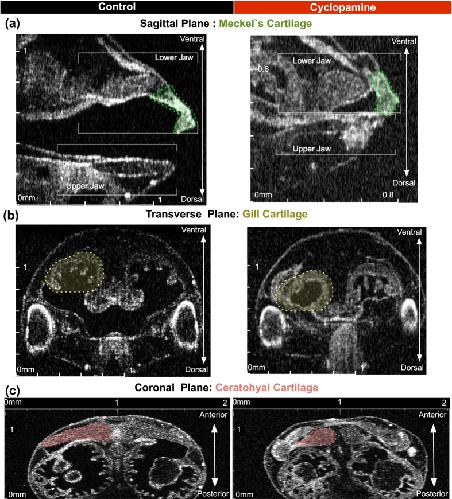

Figure 4. Qualitative neural crest defects in Xenopus with cyclopamine treatment.Stage 46 uninjected control tadpole compared to cyclopamine treated tadpoles and demonstrated the teratogenic effects. (aâc) Left column shows the control and the right column shows the cyclopamine treated tadpole. In cyclopamine treated tadpoles both jaws were short and thick. Meckel and ceratohyalcartilage were smaller and gill cartilages were nearly lost. (Scale Bar on x and y axis: 0â2âmm).